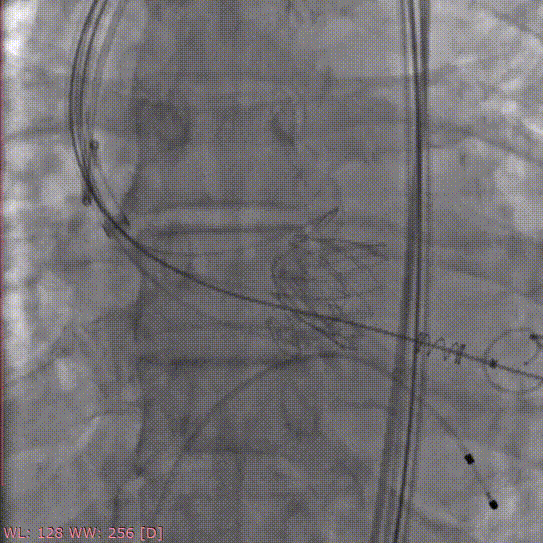

定位件入窦

释放瓣膜

手术过程和结果

术中采用局部麻醉,经股动脉穿刺建立血管通路,首先采用22mm球囊对病变部位进行预扩张,预扩时无明显腰征及反流,之后将杰成主动脉瓣输送器送入主动脉瓣目标位置,轻松实现定位件的正确入窦,后成功释放22mm瓣膜,之后采用22mm球囊进行后扩张,整个手术过程行云流水,仅用时20分钟。经DSA造影和超声等综合评估显示瓣膜释放位置完美,瓣膜工作稳定,术后即刻主动脉瓣上峰值流速:204cm/s、峰值压力阶差:16mmHg,平均压差:8mmHg,人工主动脉瓣瓣环内无反流,微量瓣周漏,患者临床症状和血流动力学明显改善。